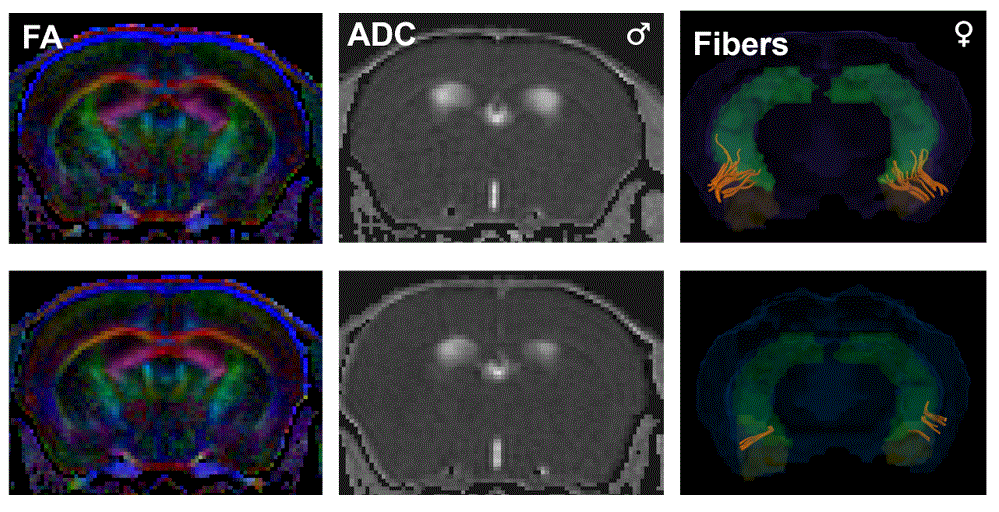

In our recent study published in Translational Psychiatry, we investigated this question using a powerful mouse model of ASD. What we found was striking: male and female mice with the same genetic mutation showed similar behavioral problems, but the brain networks behind those problems were completely different. This discovery could help explain why autism looks different in boys and girls, and it offers new insights into the neural circuits involved in social behavior.

To find out, we combined behavioral tests and neuroimaging tools. This lets us map functional networks across the cortex, essentially, how different regions of the brain "talk" to each other during social behaviors.

Even though both male and female mutant mice showed similar behavioral impairments (like reduced interest in social interaction), the underlying brain networks were quite different.

This sex-specific brain mapping suggests that males and females may “arrive” at the same social symptoms through different neural pathways — a concept known as "different roads to the same destination."